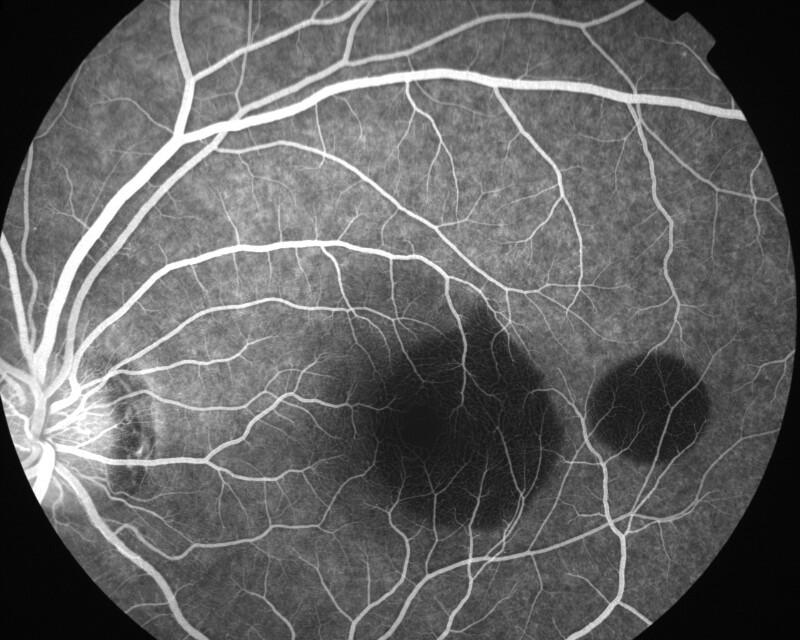

IMG0019.jpg